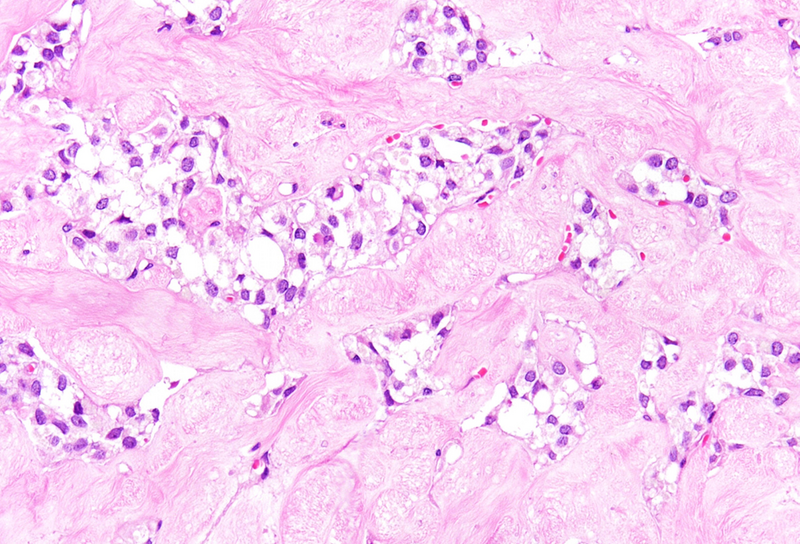

Histological examination revealed a well-circumscribed neoplasm with a fibrous capsule (Panel A), composed of uniform, poorly cohesive cells arranged in both solid (Panel B) and pseudopapillary structures (Panel C). The pseudopapillae resulted from degenerative changes leading to detachment of tumor cells from another and from central fibrovascular cores. Stromal hyalinization was also noted (Panel D). The neoplastic cells were monomorphic, with round to oval nuclei showing finely dispersed chromatin, inconspicuous nucleoli, and moderate amounts of eosinophilic to clear cytoplasm. Mitoses were not seen.